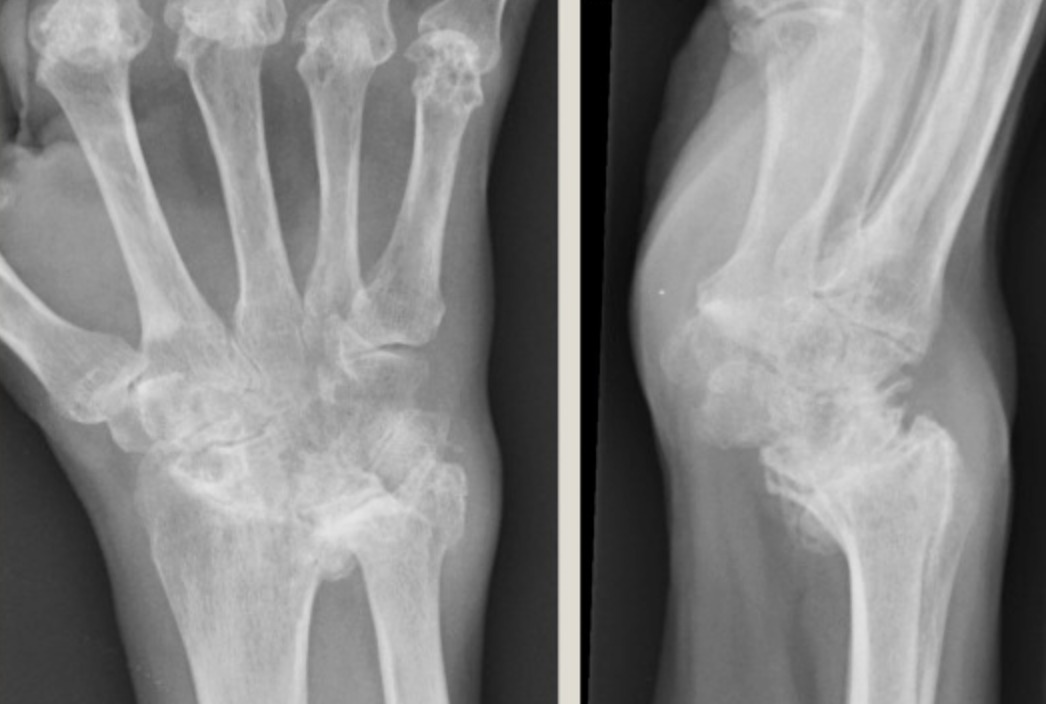

SLAC Wrist (Scapholunate Advanced Collapse) | The most common pattern. Progressive arthritis following chronic scapholunate ligament disruption. Stage I: Radial styloid-scaphoid arthritis. Stage II: Entire radioscaphoid joint. Stage III: Capitolunate joint. |

SNAC Wrist (Scaphoid Non-union Advanced Collapse) | Similar collapse pattern following untreated scaphoid non-union. Avascular necrosis of the proximal pole is often present. |

Kienböck’s Disease (Avascular Necrosis of Lunate) | Progressive collapse of the lunate bone following disruption of its blood supply. Classified by Lichtman staging (I–IV). Can progress to pancarpal arthritis. |